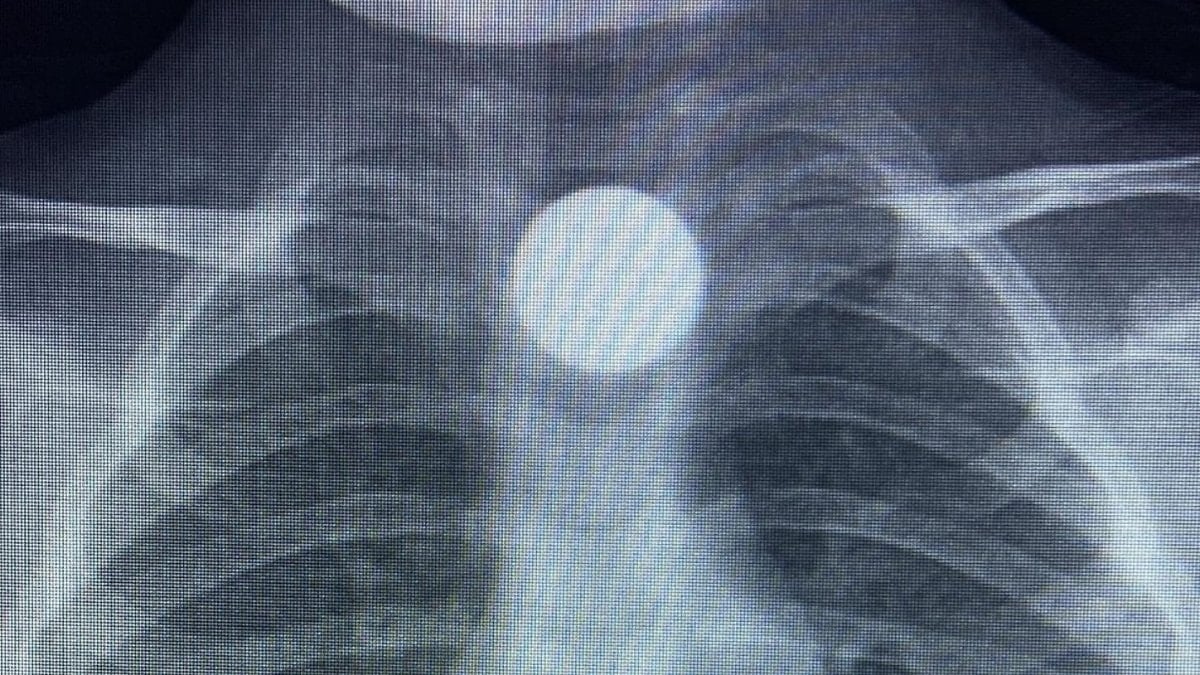

Çocuğun parayı yuttuğunu fark eden ailesi, Bilal K.’yi vakit kaybetmeden özel araçla İnegöl Devlet Hastanesi’ne götürdü. Hastanede yapılan muayene ve görüntüleme işlemlerinde, madeni paranın çocuğun yemek borusunda takılı kaldığı tespit edildi.

İlk müdahalesi İnegöl Devlet Hastanesi’nde yapılan Bilal K., ileri tetkik ve tedavi amacıyla ambulansla Bursa Yüksek İhtisas Eğitim ve Araştırma Hastanesi’ne sevk edildi.